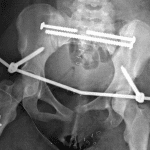

- Acute laterally displaced fracture of the left inferior pubic ramus as well as fractures of the pubic body and superior pubic ramus with slight counterclockwise rotation of the left hemipelvis and widening of the left sacroiliac joint

- Left superior pubic ramus fracture extends into the pubic symphysis

- Acute traumatic central left hip dislocation with the left femoral head dislocated into the anatomic pelvis

- Disruption of the left second sacral arch

- Mildly displaced tiny marginal avulsion fracture of the superior ilium at the sacroiliac joint

- Acute minimally displaced transverse fracture of the right acetabulum

- Acute nondisplaced fracture of the right inferior pubic ramus

- Large wound in the left groin with subcutaneous gas in the left thigh

- Unstable pelvic ring injury (LC III)

Acute, open, unstable pelvic ring injuries (lateral compression type III / LC III) and central left hip dislocation, as discussed below:

Acute left obturator ring fractures including a laterally displaced fracture of the left inferior pubic ramus and fractures of the pubic body and superior pubic ramus. Slight counterclockwise rotation of the left hemipelvis and widening of the left sacroiliac joint. Left superior pubic ramus fracture extends into the pubic symphysis without symphyseal diastasis. Mildly displaced tiny marginal avulsion fracture of the superior ilium at the sacroiliac joint.

Disruption of the left second sacral arch indicating an acute Denis zone 2 fracture.

Acute traumatic central left hip dislocation with the left femoral head dislocated into the anatomic pelvis.

Acute minimally displaced transverse fracture of the right acetabulum.

Acute nondisplaced fracture of the right inferior pubic ramus.

Large wound in the left groin with subcutaneous gas in the left thigh.